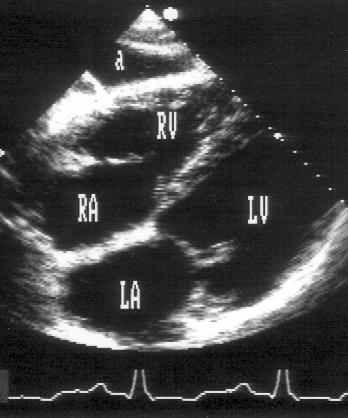

Субкостальная позиция длинной оси сердца (рис. 2.16)

Для регистрации субкостальной позиции длинной оси сердца датчик устанавливают под мечевидным отростком и центральный ультразвуковой луч направляют вверх и влево. Плоскость датчика поворачивают таким образом, чтобы она проходила через длинную ось сердца. Эта позиция похожа на апикальную четырехкамерную позицию сердца: она позволяет рассмотреть все четыре камеры сердца, трехстворчатый и митральный клапаны. Имеются определенные трудности в получении субкостальной позиции длинной оси сердца, связанные с тем, что эта позиция, как никакая другая, требует отклонения датчика без потери контакта его с поверхностью тела.

Рисунок 2.16. Субкостальная позиция длинной оси сердца. LV — левый желудочек, RV — правый желудочек, LA — левое предсердие, RA — правое предсердие, a — асцит.

На изображении правые отделы сердца оказываются ближе к датчику, — правое предсердие слева, правый желудочек справа. Правее и ниже находятся левый желудочек и левое предсердие. Субкостальная позиция длинной оси сердца получена правильно, если регистрируется максимальное открытие створок митрального и трехстворчатого клапанов. Субкостальная позиция длинной оси сердца — единственная из эхокардиографических позиций, в которой межжелудочковая и межпредсердная перегородки расположены почти перпендикулярно ультразвуковому лучу. Поэтому эта позиция оптимальна для диагностики дефектов межжелудочковой и особенно межпредсердной перегородки, которую вообще относительно трудно рассмотреть при трансторакальном исследовании.